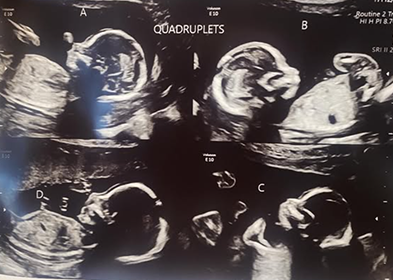

At their initial appointment, the ultrasound revealed another surprise.

“I’m a doula and a midwife assistant so I know what to look for,” Kayleen remarked about that day last July when she and Zeke viewed the ultrasound images on the screen. Little by little, they noticed something that didn’t appear in previous ultrasounds: “We started counting,” Kayleen recalled, “and let’s just say I was glad I was already lying down.”

Upon seeing the fuzzy black and white images, Zeke had to steady himself, almost passing out upon learning there were not three babies, but four.

Experts say there’s a 1-in-700,000 chance of quadruplets being conceived naturally. But the Delgado quadruplets were even more rare. There were three identical babies sharing one amniotic sack and a single baby in another. Each sack had its own placenta. That made this pregnancy one in a million.